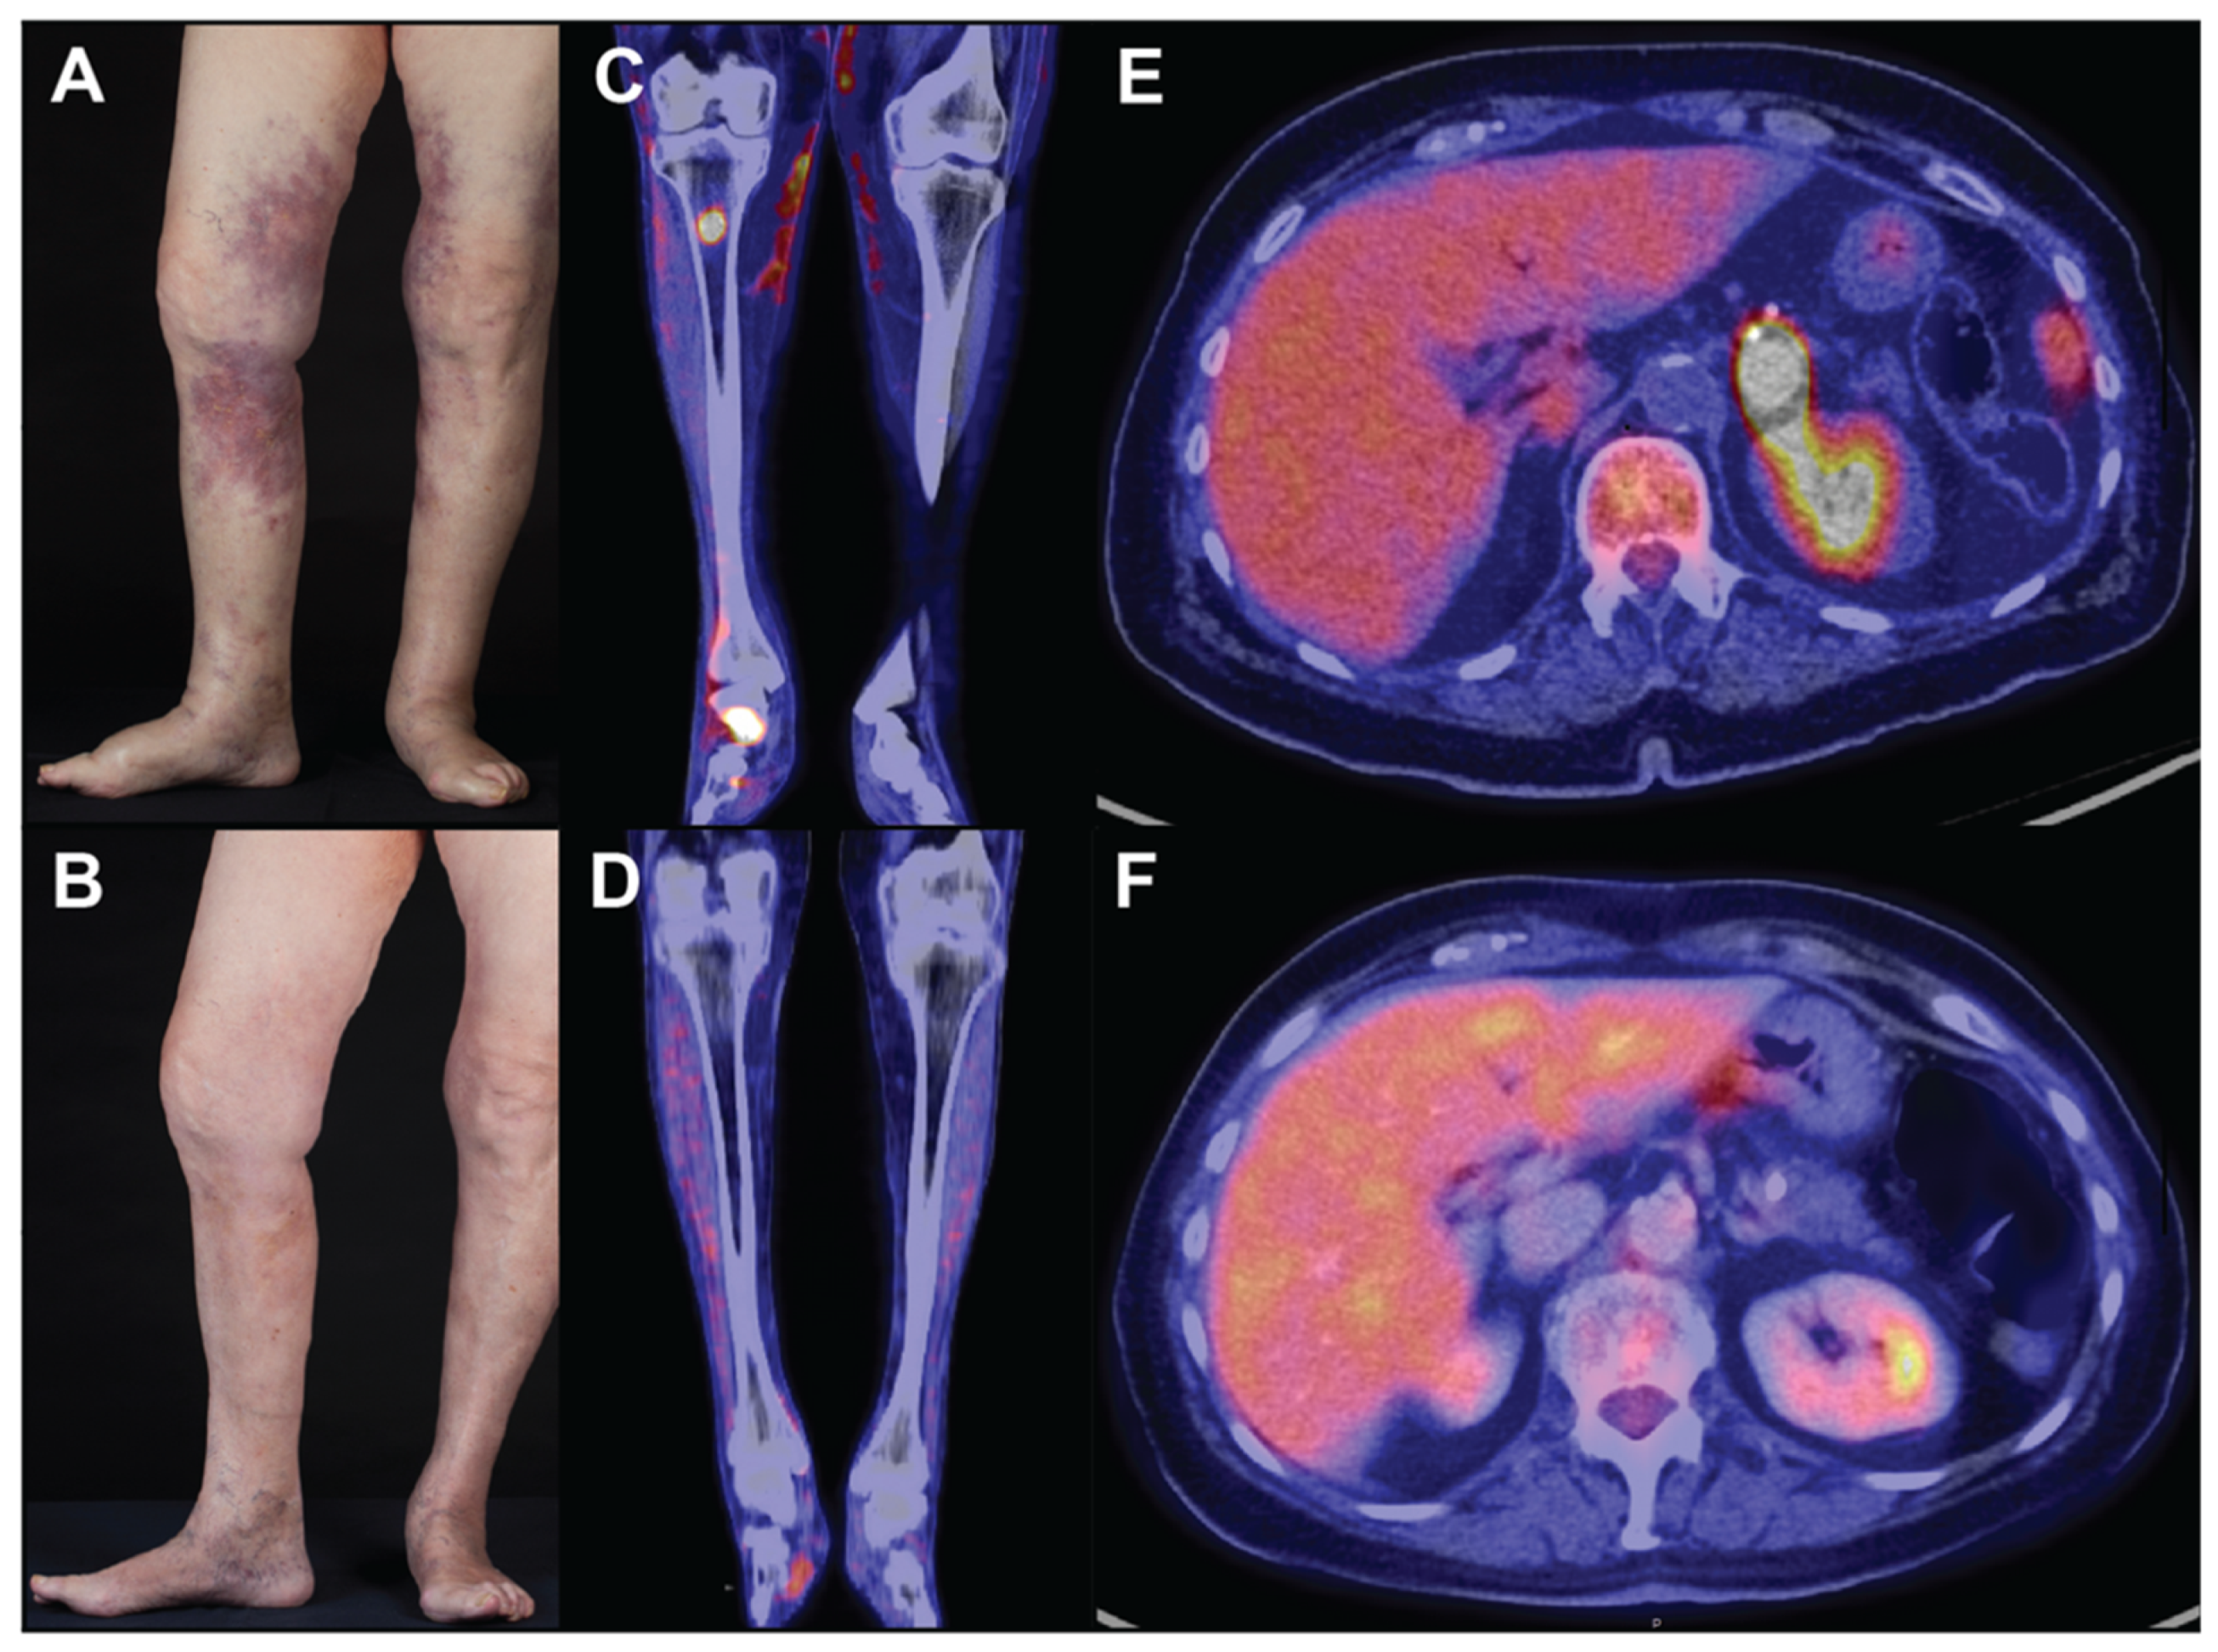

2. Extracutaneous Clinical Presentation

3. Skin Findings